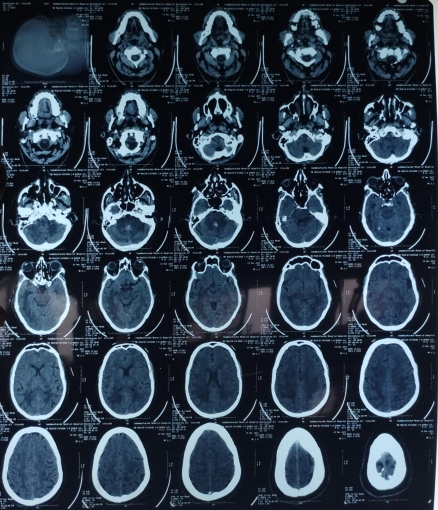

The patient’s routine blood investigations were normal. Serology for HIV, hepatitis B, C, and syphilis was negative. His MRI brain showed a parenchymal bleed in right temporo occipital regions with intra-ventricular leakage of blood and tiny petechial haemorrhage in brain parenchyma bilateral. extensive signal changes in cerebellar hemisphere, bilateral gangliothalamocapsular region, pons, midbrain and deep white matter of both cerebral hemisphere? Microangiopathy? CADASIL.

Early-onset dementia (onset before age 65) is a thought-provoking ailment with many possible causes, including early-onset familial Alzheimer’s disease, frontotemporal lobar degeneration, Parkinson’s dementia, Lewy body dementia, disorders of amino acid and organic acid metabolism, leukodystrophies, lysosomal storage diseases, disorders of metal metabolism, and mitochondrial diseases [6]. In our patient, the history, physical examination, laboratory investigations, and neuroimaging were not suggestive of these causes and prompted the search for a rare etiology. The most common MRI finding associated with CADASIL is basal ganglia and white matter hyperintensities in T2-weighted sequences that start as punctate or nodular foci and then often become confluent, extensive, and usually symmetrical, mainly in the periventricular region, anterior temporal pole, external capsule, the centrum semiovale, and frontal and parietal areas. In our patient, diagnosis was made mainly from MRI findings as seen in fig. 1, 2.

Fig. 1: Tiny petechial hemorrhages are seen in bilateral basal ganglia, white matter of both cerebral hemisphere, midbrain, pns and cerebellum. Diffuse cerebral and cerebellar atrophy is seen with enlarged ventricle due to atrophy. Acute to subacute parenchymal bleed is seen in righttemporo–occipital region. minimal intraventricular leakage of blood is also seen in 4th ventricle